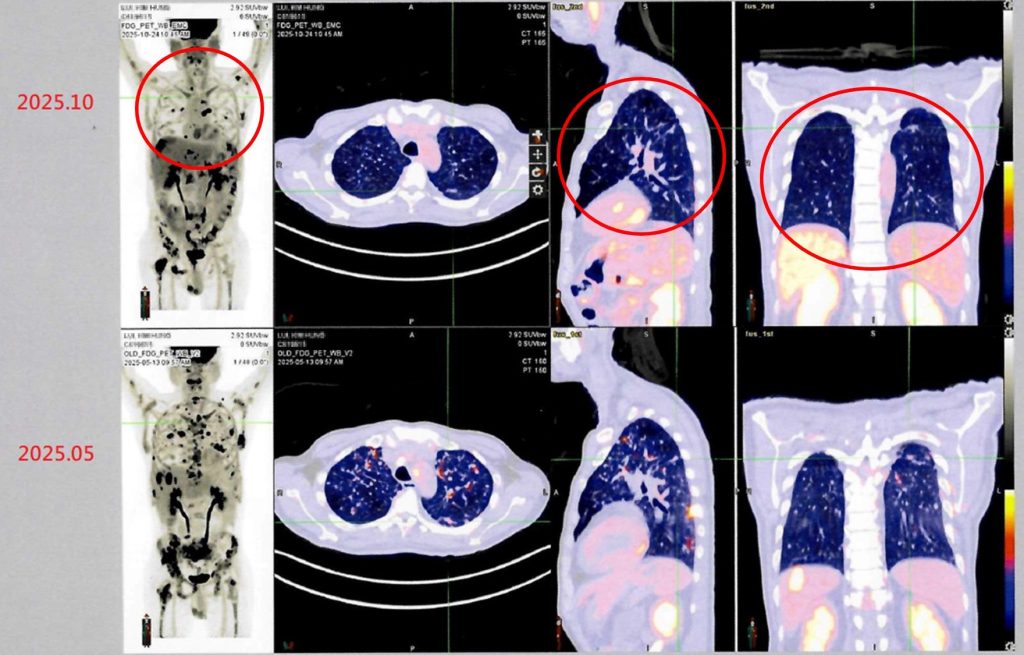

衛生福利部雙和醫院有位來自香港的男性病患(50歲)。他於2024年在香港被診斷出罹患第四期肺癌,歷經多次傳統化療與標靶治療後,為尋求新的治療機會,他評估後決定來台灣進行自體免疫細胞治療(DC-CIK)。經過半年整合療程後,最新影像檢查顯示病情穩定,疼痛症狀明顯獲得緩解,體能與生活品質大幅提升。